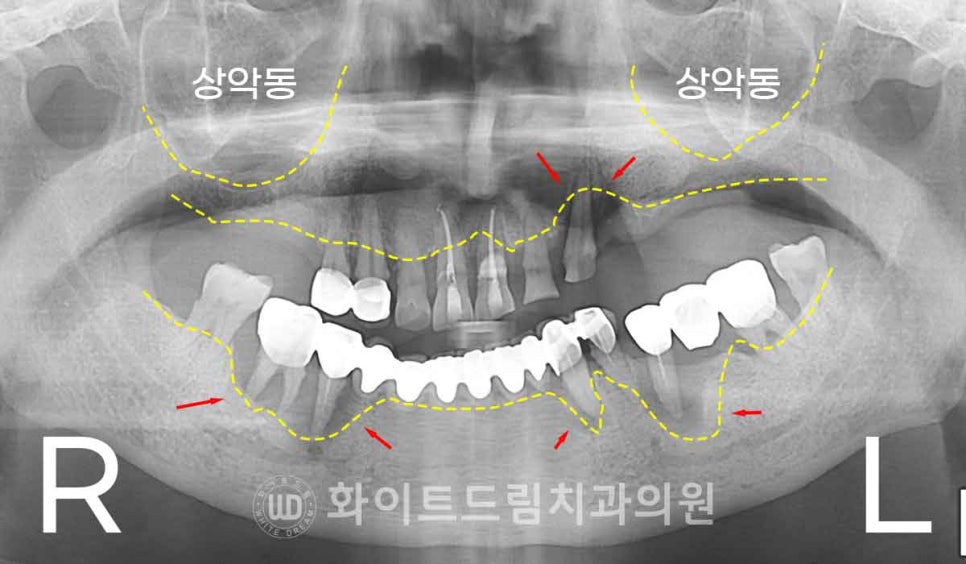

▲ 환자분의 치료 전 X-RAY 사진입니다.

상/하악 치아들이 더 이상 사용이 불가능할 정도로 심한 치아 마모와 손상을

입은 상태이고 하악 롱브릿지로 연결되어 있는 지대치는

심한 치주염으로 광범위한 뼈 흡수가 진행된 것이 확인됩니다.

▲ 롱브릿지 치료가 되어 있는 부위가

다른 치아들보다 잇몸 염증이 심하게 나타나고,

주변의 잇몸뼈 파괴도 더 광범위하게 진행된 것을 볼 수 있습니다.